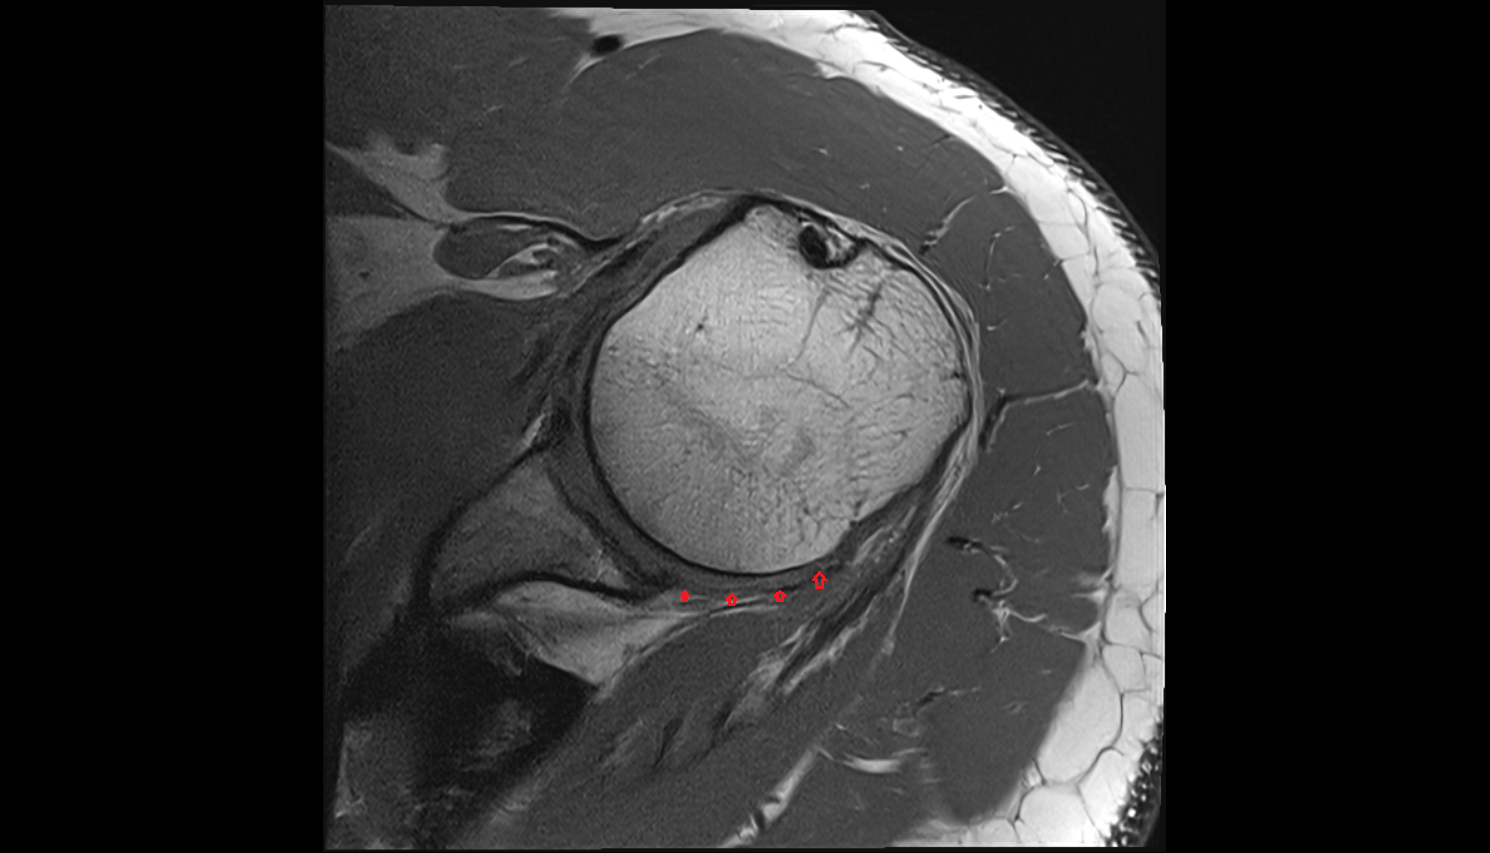

- Glenoid labrum

- Shoulder joint (glenohumeral joint)

- Glenohumeral joint capsule

- Supraspinatus tendon

- Infraspinatus tendon

- Subscapularis tendon